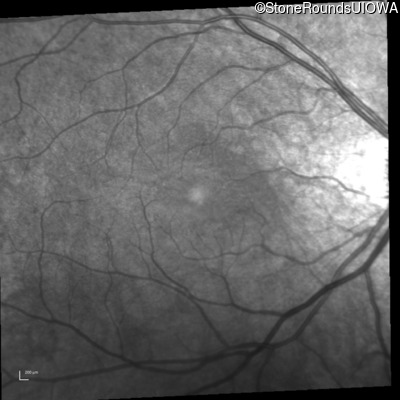

Infrared Fundus Photograph - Right - 20/50 +2

Exemplar